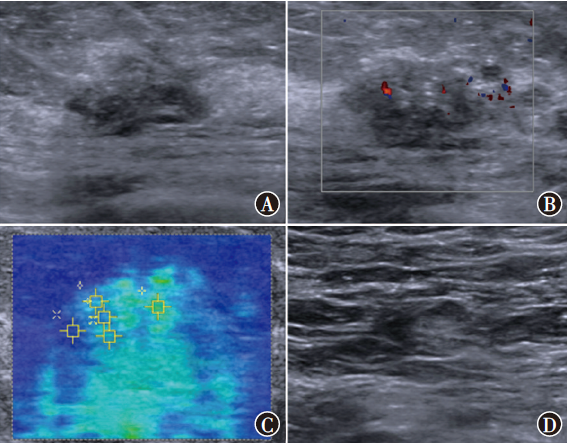

目的 探讨常规超声联合剪切波弹性成像(SWE)鉴别诊断非肿块型导管原位癌(DCIS)和浸润性乳腺癌(IBC)的价值。方法 选取2019年3月至2022年4月在南京大学医学院附属鼓楼医院收治的102例非肿块型乳腺癌患者作为研究对象,其中DCIS 32例、IBC 70例。比较非肿块型DCIS、IBC患者常规超声参数回声、微钙化、方位、后方回声、血流、腋窝淋巴结、乳腺影像报告与数据系统(BI-RADS)评分及SWE相关参数剪切波速度最大值(SWVmax)、剪切波速度最小值(SWVmin)、剪切波速度平均值(SWVmean)和剪切波速度中位数(SWVmedian),采用二元logistic回归分析鉴别诊断非肿块型DCIS和IBC的独立影响因素。根据多因素分析结果构建列线图预测模型,采用受试者操作特征(ROC)曲线评估预测模型的预测效能,采用校准曲线及决策曲线分析(DCA)评估模型的准确性和实用性。结果 非肿块型DCIS、IBC患者间血流(χ2=8.47,P=0.004)、腋窝淋巴结(χ2=9.11,P=0.003)、SWVmaxZ=-3.32,P<0.001)、SWVmeant=3.00,P=0.003)、SWVmedianZ=-2.69,P=0.007)差异均有统计学意义。多因素分析显示,血流(OR=3.56,95%CI为1.28~9.89,P=0.015)、腋窝淋巴结(OR=3.04,95%CI为1.10~8.42,P=0.032)和SWVmaxOR=1.40,95%CI为1.13~1.73,P=0.002)均为鉴别诊断非肿块型DCIS和IBC的独立影响因素。基于血流、腋窝淋巴结、SWVmax构建列线图预测模型。ROC曲线分析显示,血流、腋窝淋巴结、SWVmax、预测模型鉴别诊断非肿块型DCIS和IBC的曲线下面积分别为0.64(95%CI为0.52~0.76)、0.66(95%CI为0.55~0.77)、0.71(95%CI为0.60~0.81)、0.79(95%CI为0.70~0.88),预测模型的鉴别诊断价值高于血流(Z=2.92,P=0.004)、腋窝淋巴结(Z=2.94,P=0.003)、SWVmaxZ=1.88,P=0.060)单独诊断。预测模型鉴别诊断非肿块型DCIS和IBC的C-index为0.77,校准曲线显示模型的预测概率接近实际概率。DCA表明,该模型能提供较高的临床净获益,具有一定的临床实用性。结论 常规超声参数中的血流、腋窝淋巴结和SWE相关参数的SWVmax均为鉴别诊断非肿块型DCIS和IBC的独立影响因素,以此构建的列线图预测模型对非肿块型DCIS和IBC具有较高的鉴别诊断价值。

Objective To investigate the value of conventional ultrasound combined with shear wave elastography (SWE) in the differential diagnosis of non-mass ductal carcinoma in situ (DCIS) and invasive breast cancer (IBC). Methods A total of 102 patients with non-mass breast cancer admitted to Nanjing Drum Tower Hospital, Affiliated Hospital of Nanjing University Medical School from March 2019 to April 2022 were selected as the study objects, including 32 cases of DCIS and 70 cases of IBC. Conventional ultrasound parameters echo, microcalcification, location, posterior echo, blood flow, axillary lymph node, breast imaging reporting and data system (BI-RADS) score and SWE-related parameters maximum shear wave velocity (SWVmax), minimum shear wave velocity (SWVmin), mean shear wave velocity (SWVmean) and median shear wave velocity (SWVmedian) were compared between patients with non-mass DCIS and IBC. Binary logistic regression was used to analyze the independent factors for the differential diagnosis of non-mass DCIS and IBC. Based on the results of multivariate analysis, a nomogram prediction model was constructed and the predictive efficacy of the prediction model was evaluated by receiver operator characteristic (ROC) curve. Calibration curve and decision curve analysis (DCA) were used to evaluate the accuracy and practicability of the model. Results There were statistically significant differences in blood flow (χ2=8.47, P=0.004), axillary lymph nodes (χ2=9.11, P=0.003), SWVmaxZ=-3.32, P<0.001), SWVmeant=3.00, P=0.003), SWVmedianZ=-2.69, P=0.007) between patients with non-mass DCIS and IBC. Multivariate analysis showed that, blood flow (OR=3.56, 95%CI: 1.28-9.89, P=0.015), axillary lymph nodes (OR=3.04, 95%CI: 1.10-8.42, P=0.032) and SWVmaxOR=1.40, 95%CI: 1.13-1.73, P=0.002) were independent factors for distinguishing non-mass DCIS from IBC. A nomogram prediction model was constructed based on blood flow, axillary lymph nodes and SWVmax. ROC curve analysis showed that, the area under the curve of blood flow, axillary lymph nodes, SWVmax, and prediction model for differential diagnosis of non-mass DCIS and IBC were 0.64 (95%CI: 0.52-0.76), 0.66 (95%CI: 0.55-0.77), 0.71 (95%CI: 0.60-0.81), and 0.79 (95%CI: 0.70-0.88), respectively, and the differential diagnostic value of prediction model was higher than that of blood flow (Z=2.92, P=0.004), axillary lymph nodes (Z=2.94, P=0.003), and SWVmaxZ=1.88, P=0.060) alone. The C-index of the prediction model for the differential diagnosis of non-mass DCIS and IBC was 0.77, and the calibration curve showed that the prediction probability of the prediction model was close to the actual probability. DCA showed that this prediction model could provide higher clinical net benefit and had certain clinical practicability. Conclusion Blood flow and axillary lymph nodes in conventional ultrasound parameters and SWVmax of SWE-related parameters are independent factors in the differential diagnosis of non-mass DCIS and IBC. The nomogram prediction model constructed by this method has a high value in the differential diagnosis of non-mass DCIS and IBC.